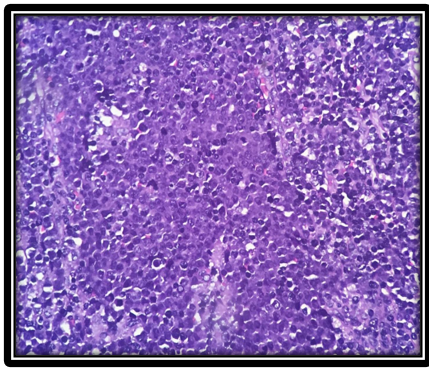

On histopathological evaluation, non-Hodgkin lymphoma without further subtyping was the most common diagnosis (33/48 = 68.75%). Among cases where subtyping was performed based on histomorphology, follicular lymphoma (3/48 = 6.25%) and diffuse large B-cell lymphoma (DLBCL) (3/48 = 6.25%) were equally common. Diagnostic frequencies are presented in Table 4. Representative histopathological images of DLBCL and follicular lymphoma are shown in Figure 1 and Figure 2, respectively.

On histopathological evaluation, non-Hodgkin lymphoma without further subtyping was the most common diagnosis (33/48 = 68.75%). Among cases where subtyping was performed based on histomorphology, follicular lymphoma (3/48 = 6.25%) and diffuse large B-cell lymphoma (DLBCL) (3/48 = 6.25%) were equally common. Diagnostic frequencies are presented in Table 4. Representative histopathological images of DLBCL and follicular lymphoma are shown in Figure 1 and Figure 2, respectively.